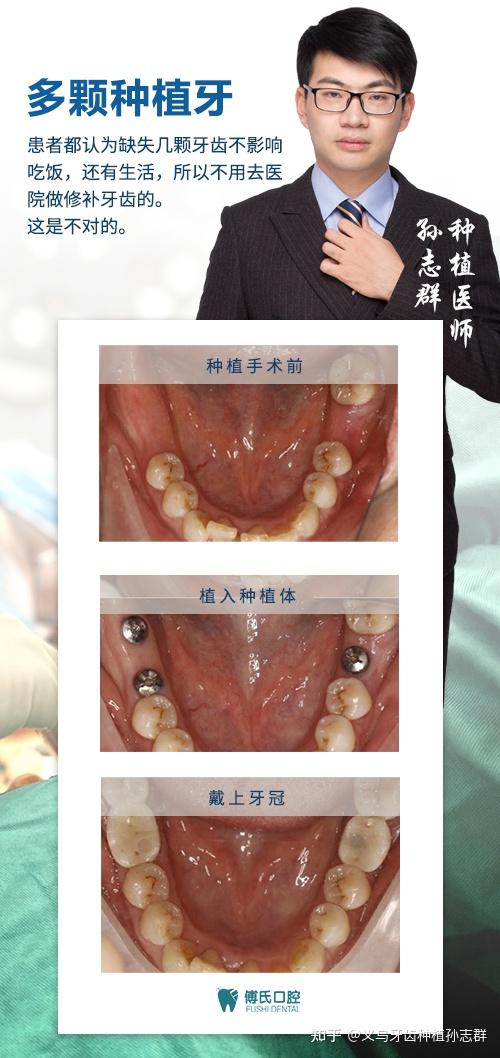

义乌牙齿种植孙志群医师义乌牙齿种植孙志群

图片尺寸500x1058

连种两颗牙的种植牙案例(缺两颗牙齿,植入种植体,修复牙冠)